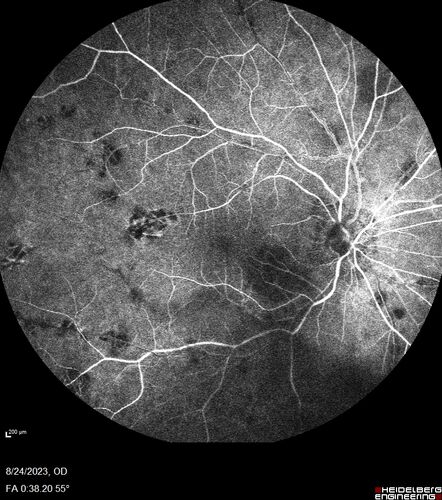

West Nile Virus Multifocal Choroiditis with later CNVM

77 year old female with vision loss in the left eye treated with Anti-VEGF